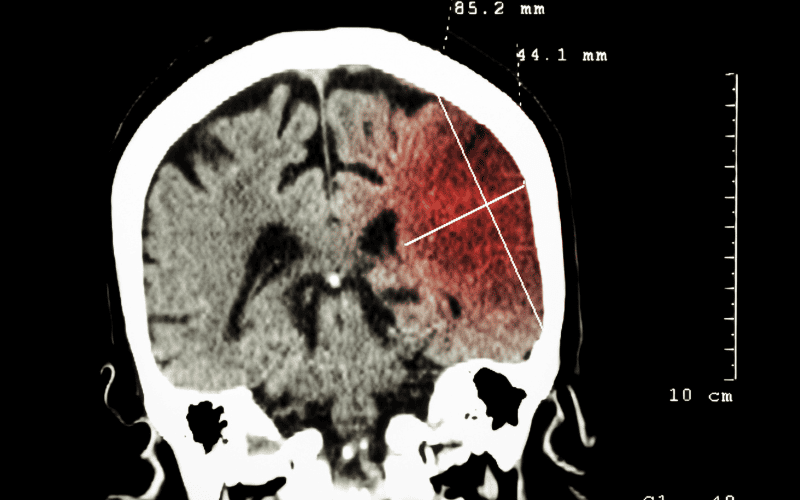

- CT scan hoặc MRI: Giúp hình ảnh hóa não bộ và phát hiện tổn thương hoặc triệu chứng liên quan.